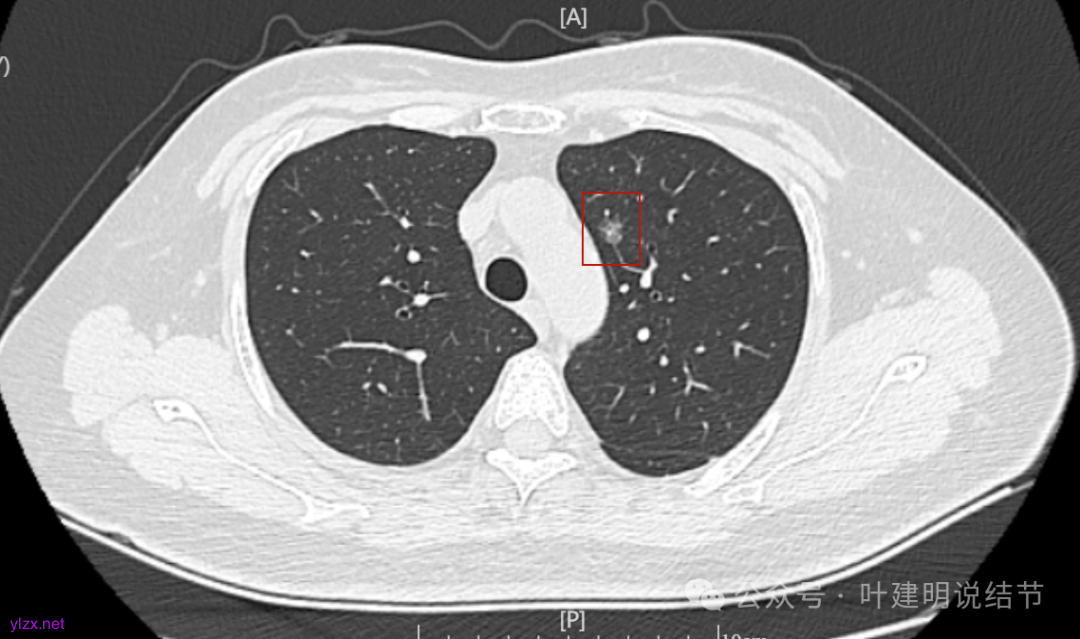

12.2025年4月复查,显示最大结节0.9*0.7。 另外,看几次报告,多发磨玻璃结节数量在上升,从2022年的3个到2025年的7个。

两肺多发磨玻璃结节,主病灶混合密度且有小血管进入,表面不平有毛刺,考虑微浸润性腺癌或浸润性腺癌可能性大,其余部分考虑原位癌或微浸润性腺癌,部分考虑肺泡上皮增生或不典型增生可能。总体上对比2022年说不上太明显的进展。但对于是否手术来讲,我仍倾向当年的意见,左侧的可以考虑近期亚肺叶(个人倾向楔切)切除,右侧的先随访,以后有进展并风险增加再考虑干预处理。因为要拉长两次手术的间隔,这样对机体的创伤与恢复更加有利一些。若定要仍不开刀,则建议要4-6个月复查,不过个人不太主张过于保守随访,对于像主病灶这种有少许实性成分的,不能保证肯定安全。意见供参考!